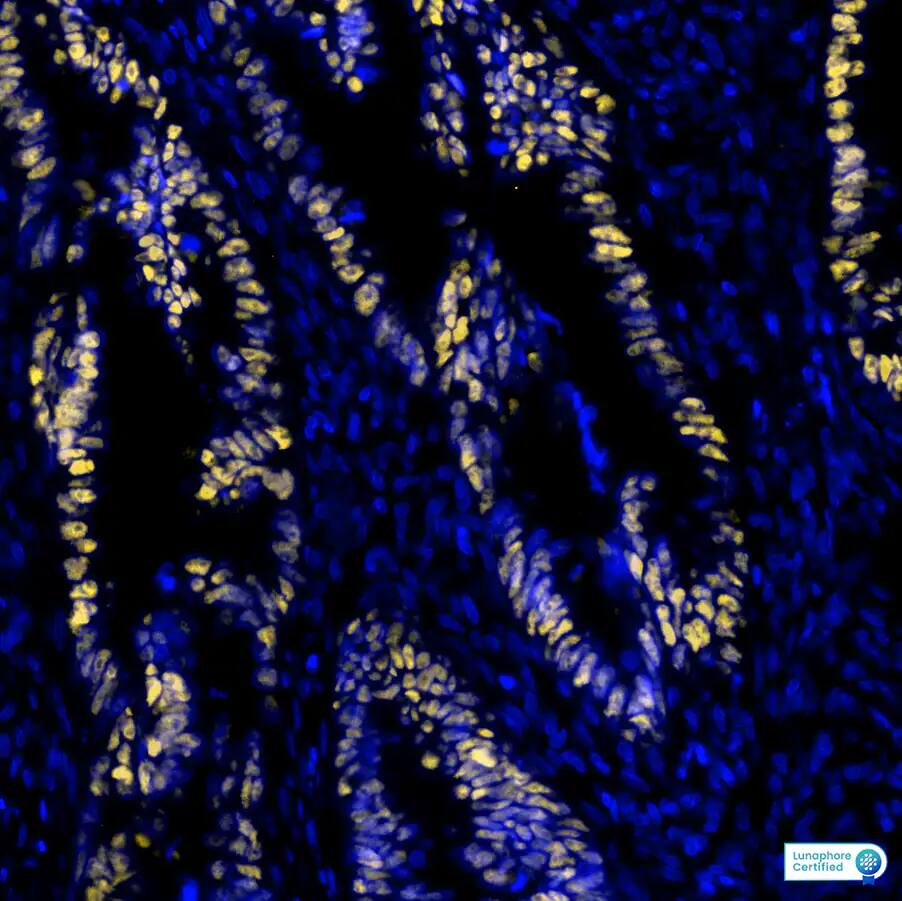

Detection of p53 in Human Colon Tumor via seqIF™ staining on COMET™

p53 was detected in immersion fixed paraffin-embedded sections of human Colon Tumor using Mouse Anti-Human p53 Monoclonal Antibody at 12ug/mL at 37°Celsius for 8 minutes. Before incubation with the primary antibody, tissue underwent an all-in-one dewaxing and antigen retrieval preprocessing using PreTreatment Module (PT Module) and Dewax and HIER Buffer H (pH 9; Epredia Catalog # TA-999-DHBH). Tissue was stained using the Alexa Fluor™ 555 Goat anti-Mouse IgG Secondary Antibody at 1:100 at 37°Celsius for 2 minutes. (Yellow; Lunaphore Catalog # DR555MS) and counterstained with DAPI (blue; Lunaphore Catalog # DR100). Specific staining was localized to the astrocytes showing nuclear staining. Protocol available in COMET™ Panel Builder.